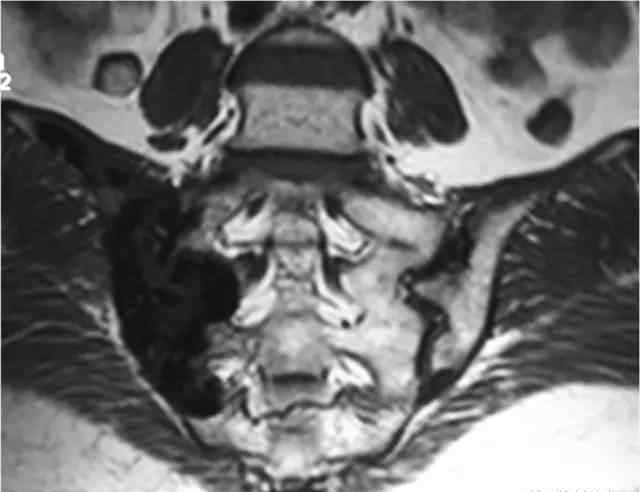

临床病史,女,60岁。主要原因是骶尾部疼痛20多年,20多年前骶尾部疼痛无诱因,为针刺样疼痛,辐射至右下肢,局部诊断为“坐骨神经痛”。体检:各椎体棘突、椎旁、双侧骶髂关节未见明显压痛和扣痛。皮肤无静脉扩张,皮肤温度不高。

图像:

手术记录:术中发现肿瘤累及髂骨、骶髂关节和部分骶骨,大小约12x10x10cm,肿瘤内含有钙质组织。

病理结果:(右侧骶髂关节)结核伴钙化